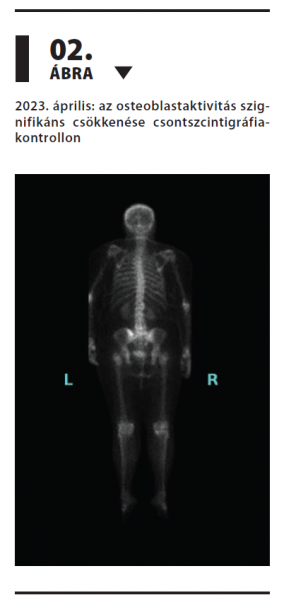

Tripla-negatív metasztatikus emlőrák hosszan tartó, sikeres kezelése szacituzumab-govitekánnal

Az emlőrák Magyarországon továbbra is a nők leggyakoribb daganatos betegsége. A Nemzeti Rákregiszter adatai szerint 2021-ben 7656 új esetet igazoltak,1 így a daganatos halálozás egyik vezető oka hazánkban is. Az áttétes tripla-negatív emlőrák prognózisa különösen rossz, a modern kezelések ellenére is. Esetünkben egy szokatlanul hosszú ideig szacituzumab-govitekán kezelésben részesülő nőbeteg történetét mutatjuk be, relatíve jó életminőség megtartása mellett.